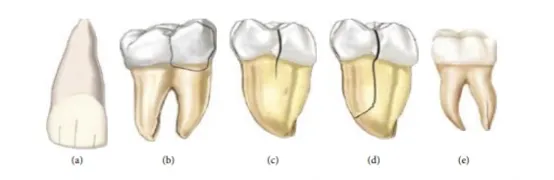

美国牙体牙髓病学协会根据裂纹位置和深度将有裂纹的牙齿分为五类:牙釉质折裂、牙尖折裂、牙隐裂、完全牙裂、根裂五类。Longridge等提出根据隐裂纹深度将牙隐裂分为釉质裂纹、牙本质裂、裂纹累及牙髓、根裂四类。由于牙隐裂临床表现复杂多样,裂纹较小或与牙齿的发育沟重叠不易被发现,所以临床上牙隐裂的诊断比较困难。目前牙隐裂主要通过病史、主诉症状和临床检查结果综合判断。一项来自国家牙科实践研究网络的研究对2858位患者的隐裂后牙进行检查,发现2/3的患者有副功能运动。临床检查方法包括透照、咬诊、叩诊、显微镜(放大14~18倍)、染色,影像学检查(如CBCT)等。Banerji等学者不推荐咬诊试验,认为应用定点力负载可能会导致隐裂牙折裂。影像学X线片检查只能侦查出53颗裂纹的证据,诊出率为约2%。影响诊出率的因素包括裂纹的大小、X线投照方向,牙本质厚度等,修复体产生的伪影也会导致隐裂部位模糊不清Yuan等研究中发现,与常规CBCT相比,增加泛影葡胺作为对比剂的锥形束CT增强扫描对检测隐裂纹的准确性的更高。近年来,光学相干断层扫描(Swept source OCT,SS-OCT)技术也可用于鉴别釉质裂纹和隐裂纹:OCT所得的影像裂纹特征明确,其敏感性和特异性与光纤透照相近,但是其穿透深度大约为3 mm左右,无法全波段定位发展到牙髓的裂纹,因此无法准确判断裂纹进展情况。

图3:隐裂牙的分类

a) 牙釉质内可见裂纹;b) 终止于牙齿颈部的断裂牙尖;c) 从咬合面延伸的牙齿破裂,而牙齿碎片没有分离;d) 分离的牙齿碎片,提示牙齿裂开;e)根部裂纹。